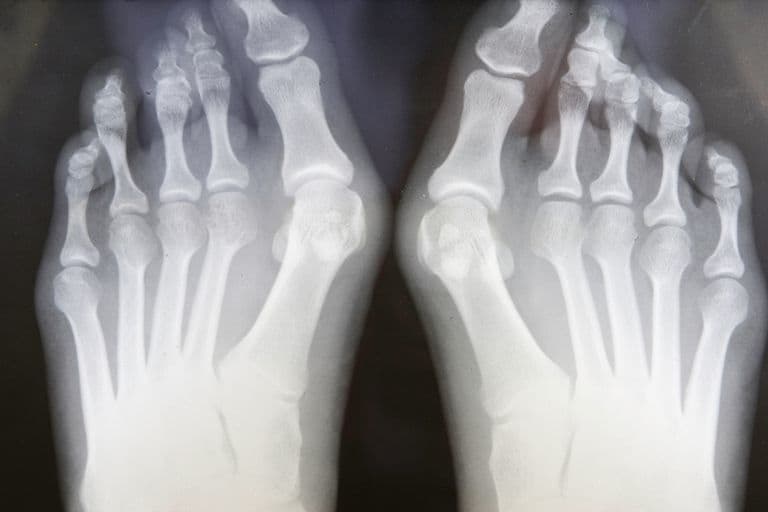

انگشت پا از کلیدیترین و حساسترین عضوهایی از بدن است که ممکن است تحت تأثیر قرار گیرد و آسیب ببیند. تورم دردناک انگشت پا ناشی از یک ضربه بر استخوان است که بر روی مفصل ایجاد میشود و در آن انگشت شست پا شما بزرگتر میشود و نام این عارضه متاتارسوفالانگه (MTP) میباشد. این امر بهآرامی در طول زمان اتفاق میافتد و درنهایت بزرگتر میشود و باقی میماند. این مورد بهنوبه خود میتواند باعث بزرگ شدن انگشت پا شود تا آنجا که گاهی اوقات در بالای انگشت پا و یا در کنار آن حرکت میکند.

پزشک شما احتمالاً میتواند فقط با نگاه کردن بهپایخود به شما بگوید که مشکل چیست، او میخواهد فقط یک آزمایش با اشعه ایکس را انجام دهید تا ببیند آیا مفصل آسیبدیده است یا خیر. همچنین میتوانید به شما بگوید که چقدر مشکل شما جدی است و احتمالاً چه چیزی باعث آن شده است که میتواند به تصمیم او برای چگونگی درمان کمک کند.